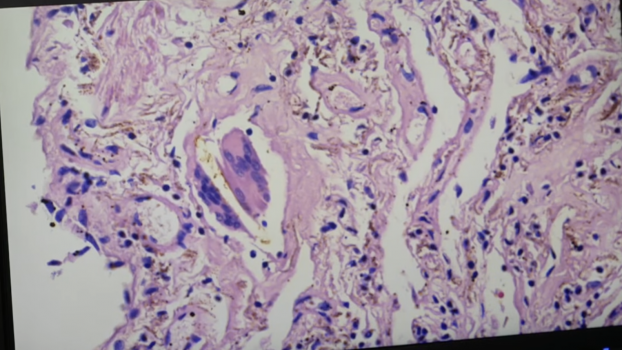

Sie sind hier: Startseite Berichte Gesundheit Politikerin fordert sofortige Prüfung der Corona-Impfstoffe Die Braunen Stellen zeigen Metall-Ablagerungen im Gewebe eines Impftoten. Bild: WB / Eigenes Werk

Die Braunen Stellen zeigen Metall-Ablagerungen im Gewebe eines Impftoten. Bild: WB / Eigenes Werk